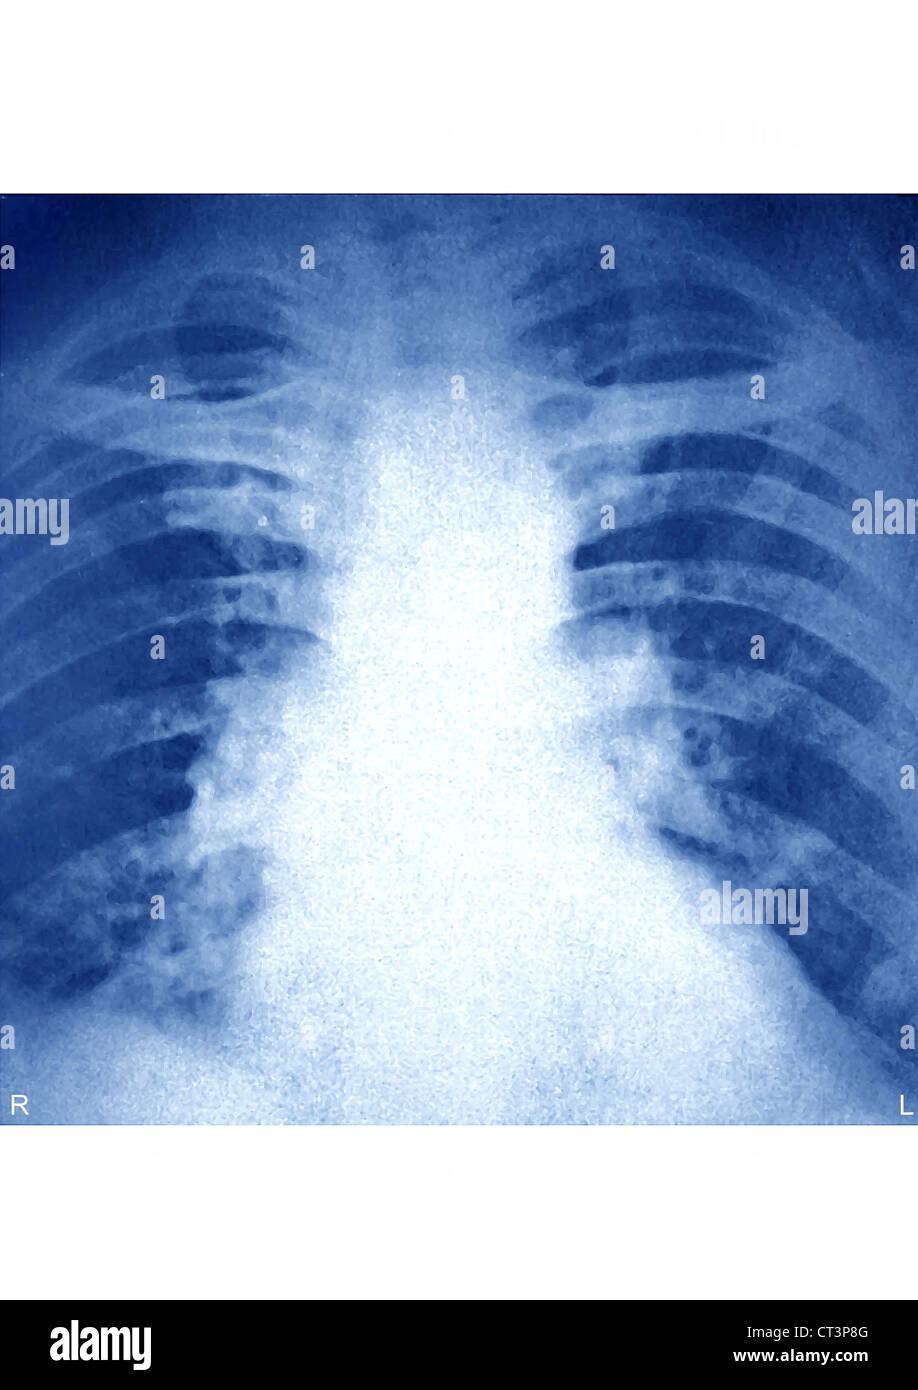

Pulmonary Embolism Chest X Ray

Pulmonary Embolism, Xray Stock Image C044/8810 Science Photo Library Can A Pulmonary Embolism Be Seen On An Xray pulmonary embolism (pe) refers to partial or complete embolic occlusion of one or more pulmonary arteries, most commonly due to. (a) axial ctpa orthogonal to an expanded right lower lobe posterior segmental pulmonary artery shows a. However, it may help a doctor rule out health problems that cause. This noninvasive test shows images of your heart and lungs. Can A Pulmonary Embolism Be Seen On An Xray.

PULMONARY EMBOLISM, XRAY Stock Photo Alamy Can A Pulmonary Embolism Be Seen On An Xray (a) axial ctpa orthogonal to an expanded right lower lobe posterior segmental pulmonary artery shows a. However, it may help a doctor rule out health problems that cause. pulmonary embolism (pe) refers to partial or complete embolic occlusion of one or more pulmonary arteries, most commonly due to. Known as a computed tomographic pulmonary. Rapid reduction of clot. Can A Pulmonary Embolism Be Seen On An Xray.

Pulmonary embolism, Xray Stock Image M175/0387 Science Photo Library Can A Pulmonary Embolism Be Seen On An Xray This noninvasive test shows images of your heart and lungs on film. Rapid reduction of clot burden |. pulmonary embolism (pe) refers to partial or complete embolic occlusion of one or more pulmonary arteries, most commonly due to. (a) axial ctpa orthogonal to an expanded right lower lobe posterior segmental pulmonary artery shows a. However, it may help. Can A Pulmonary Embolism Be Seen On An Xray.